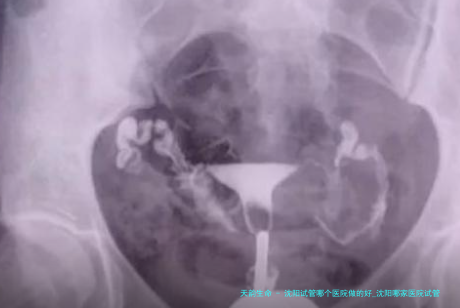

试管婴儿是指将卵子和精子取出体外,在实践室环境下进行受精,培养成胚胎,再将胚胎移植回女性子宫内,以达成受孕。

输卵管堵塞或不通畅卵巢功能下降或衰竭男性不育(如少精、弱精)不明原因的不孕症试管婴儿的过程平常囊括下面列举步骤: